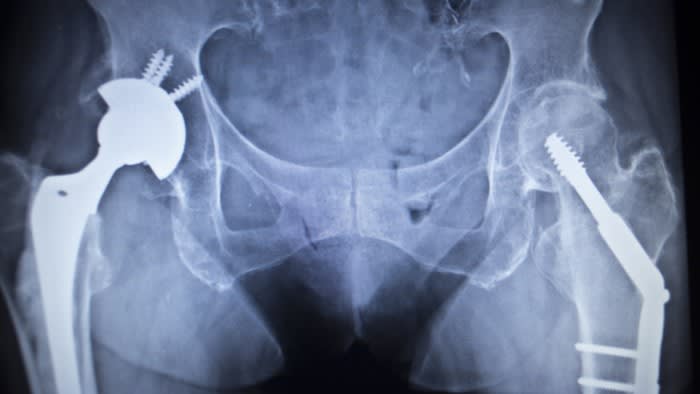

I dati del National Joint Registry, analizzati dal think-tank e condivisi con il MagicTech, hanno indicato un forte aumento in particolare delle sostituzioni dell'anca pagate privatamente, dove il totale è quasi raddoppiato da circa 17.000 nel 2019 a quasi 30.000 nel 2022. I dati del registro coprono Inghilterra, Galles e Irlanda del Nord.

La Health Foundation ha affermato che questo “avrà avuto implicazioni finanziarie sostanziali per molti dei pazienti che hanno scelto di finanziare le loro cure privatamente”, anche se “la grande maggioranza delle sostituzioni elettive dell’anca” sono ancora finanziate dal Servizio Sanitario Nazionale.

Josh Keith, vicedirettore dell'analisi dei dati presso la Health Foundation, ha affermato che, sebbene in Inghilterra si sia registrato solo un piccolo aumento nella percentuale di cure ospedaliere elettive finanziate privatamente, questa crescita è stata “notevolmente più pronunciata per alcune procedure, come le sostituzioni dell'anca”.